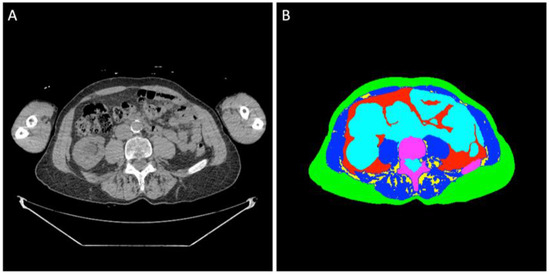

Regions of interest of the different tissues were determined at the midpoint of the L4 vertebral body using previously validated segmentation models [8]. A standard single slice was manually determined by one of the authors (MEG) with four years of experience in medical imaging and trained by senior fellowship-trained musculoskeletal radiologists (Figure 1). All segmentations were manually inspected and corrected, if necessary, by two of the authors (MEG and IZ) using Horos DICOM viewer version 3.3.6 (www.horosproject.com (accessed on 05/15/2024)). BC analysis was conducted blinded to clinical information and outcomes.

Figure 1.

(A) Non-contrast WBLDCT image at L4 level of an 80-year-old man diagnosed with SMM. (B) Semi-automated segmentation of the abdominal tissue: green label: subcutaneous adipose tissue; red label: visceral adipose tissue; yellow label: intermuscular adipose tissue; blue label: muscle tissue; turquoise label: organs, vessels, fluids; purple label: bone.